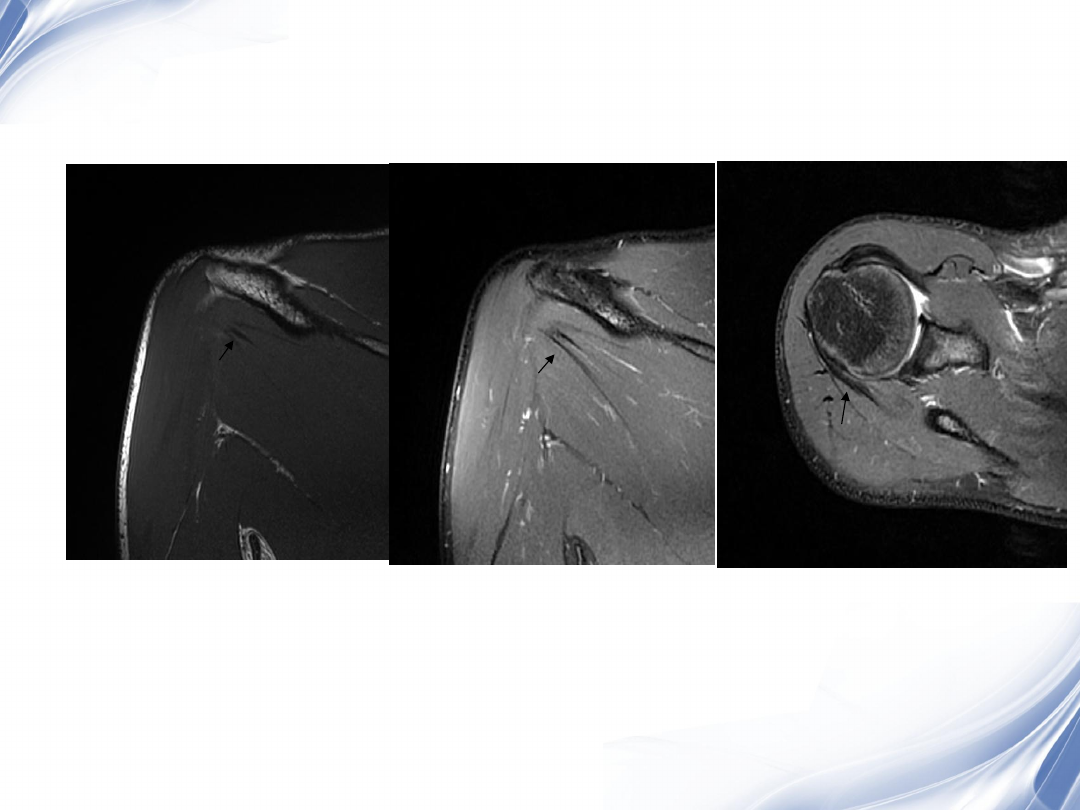

影像学检查

-MRI

最常用

斜冠状面、斜矢状面、横断面

常用的检查序列是

T1WI

T2

压脂

阳性率

95%

24

横断位

正常肩胛下肌

肩胛下肌损伤

33